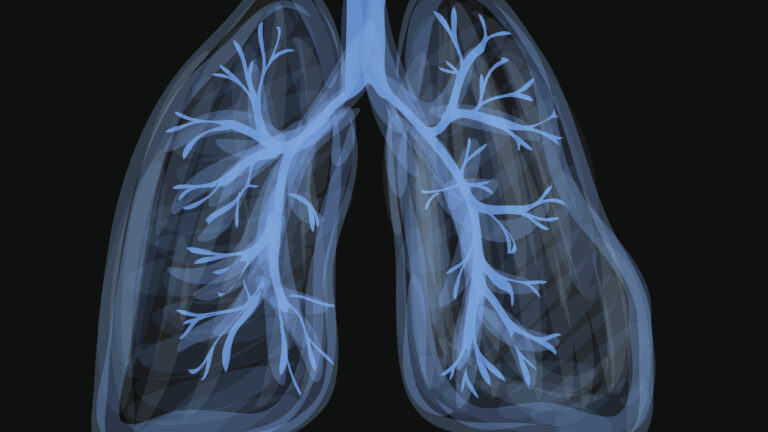

What is EVALI? Understanding the Vaping Lung Disease

EVALI lung injury refers to a severe respiratory condition directly linked to the use of e-cigarettes or vaping products. Officially termed E-cigarette or Vaping product use-Associated Lung Injury, EVALI was first recognized during a nationwide outbreak in the United States in 2019. This vape-associated lung injury causes inflammation and damage to the lungs, making it hard for them to function properly. Unlike traditional smoking-related diseases that develop slowly over years, EVALI can strike suddenly, often within days or weeks of heavy vaping.

What makes EVALI particularly insidious is its impact on otherwise healthy individuals, especially young people under 35. The condition mimics pneumonia or other infections, leading to acute or subacute respiratory failure. According to health experts, EVALI is not just a minor irritation—it’s a potentially life-threatening illness that requires immediate medical attention. If you’re searching for “what is EVALI,” know that it’s a wake-up call about the unregulated world of vaping products.

At the heart of EVALI is the toxic cocktail inhaled through vaping devices. While the exact mechanisms are still being studied, the primary culprit during the 2019 outbreak was vitamin E acetate, a thickening agent added to illicit THC-containing vaping products. This substance, when aerosolized and inhaled, irritates lung tissue, leading to chemical pneumonitis—a fancy term for lung inflammation caused by harmful chemicals.

Ongoing research highlights that even legal, regulated vaping products aren’t risk-free. Heavy or frequent use amplifies exposure to ultrafine particles, heavy metals, and volatile compounds that can scar lung tissue over time. If you’re vaping to quit smoking, consider the trade-offs—EVALI proves that “safer” doesn’t mean safe.

For many, shortness of breath from vaping starts as mild breathlessness after a session but can progress to gasping for air. Chest pain from vaping might feel like a tight band around the torso or sharp stabs, signaling inflammation in the airways. These symptoms hit hardest in the EVALI lung phase, where fluid buildup or scarring impairs oxygen exchange. If you experience these, don’t wait—EVALI can lead to respiratory failure without prompt intervention.